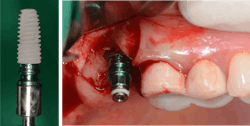

Hydraulic sinus lifting is a technological leap forward in sinus lift procedures. These innovative devices utilize hydraulic pressure to lift the sinus membrane gently and precisely, creating sufficient space for implant placement without the need for excessive bone manipulation (figure 3).